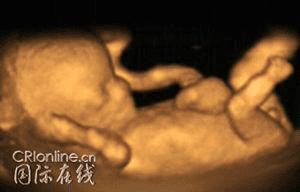

这是长到11个星期的胎儿。进入妊娠的第四个月后,胎儿从5厘米长到10厘米。

胎儿